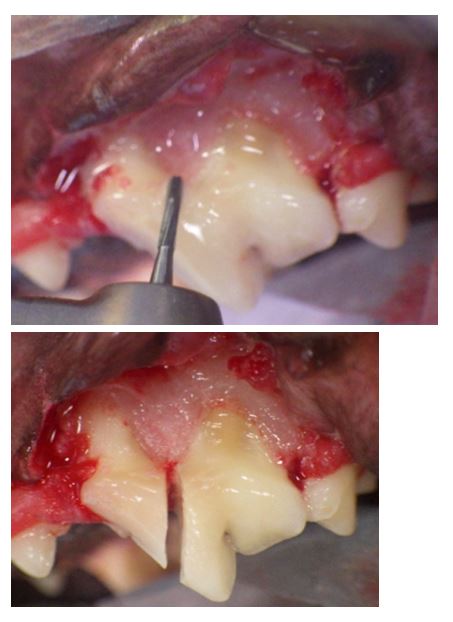

*L’extraction ouverte ou chirurgicale se caractérise par le retrait d’une partie de l’os alvéolaire se trouvant au dessus de la racine dentaire pour faciliter l’extraction de la dent. La cavité d’extraction est ensuite suturée pour une cicatrisation par première intention.

Un large lambeau d’accés permet d’aborder les tissus sous gingivaux et en particulier l’os alvéolaire recouvert de son périoste.La dissection sous périostée découvre l’os alvéolaire.

Sa découpe en plastron facilite l’extraction car la dent est cueillie dans son alvéole sans difficulté. Cette technique, l’alvéolotomie, est la technique de choix pour les avulsions de dents courbes et volumineuses (canines maxillaires de grands chiens).

*L’extraction des dents à racines multiples pose plus de problèmes en raison de la nature convergente ou divergente des racines. Il est indispensable de sectionner ces dents en autant de morceaux que de racines avant de les extraire séparément comme des dents monoradiculées . Cette séparation inter-radiculaire s’effectue soit avec une turbine équipée d’une fraise fissure soit avec un contre-angle equipé d’un disque diamanté.